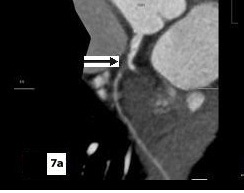

Five patients (12.5 %) had normal angiograms [Table/Fig-2,2b,3,3b], six (15%) had non-significant disease [Table/Fig-4,4b,5a,5b] and 29 patients (72.5%, 26 male & 3 female) had significant disease [Table/Fig-6a,6b],[7a,7band8] on CT coronary angiography, which was also proved on invasive angiography [Table/Fig-9]. The incidence of significant coronary detected was highest in age group of 41-60 years [Table/Fig-10].

(Sagittal), (Axial), (VRT) images & catheter angiography image showing significant stenosis in mid LAD